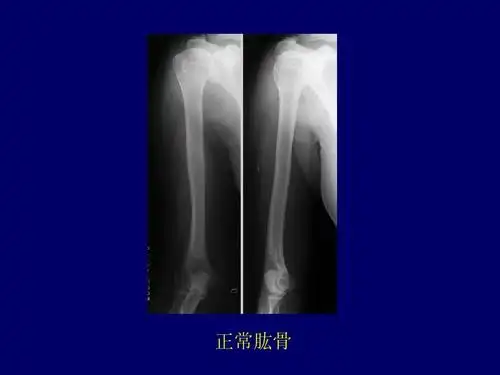

骨骼x线诊断 正常肱骨

肱骨干骨折